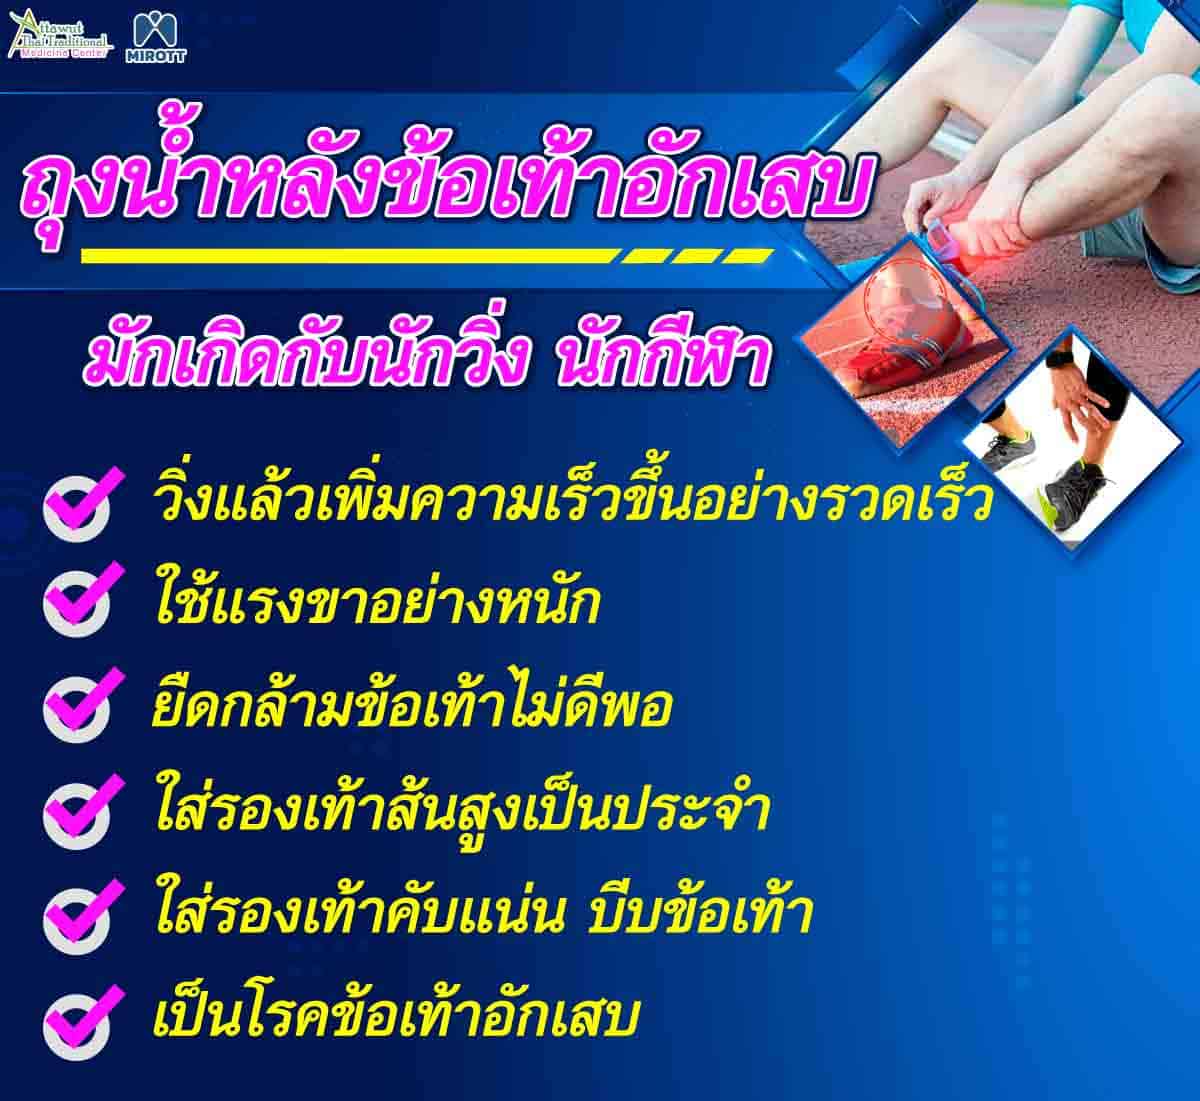

แยกให้ออก! ปวดข้อเท้าด้านหลัง เอ็นร้อยหวายอักเสบ หรือ ถุงน้ำหลังข้อเท้า … การออกกำลังกายที่ไม่เหมือนใครสำหรับเอ็นร้อยหวายและบั้นท้าย – กล้ามเนื้อ …